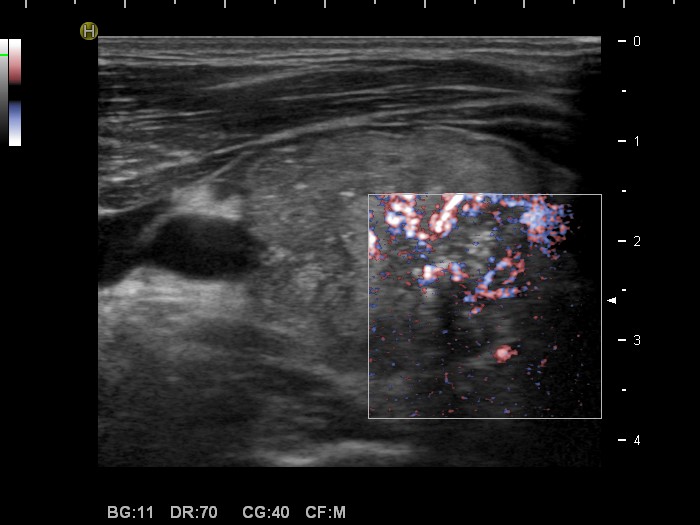

Graves' disease - Case 9. (ultrasonographic picture 5)

Right lobe, longitudinal scan

Right lobe, horizontal scan, color Doppler mode, fine flow method. The intranodular blood flow is irregularly increased.